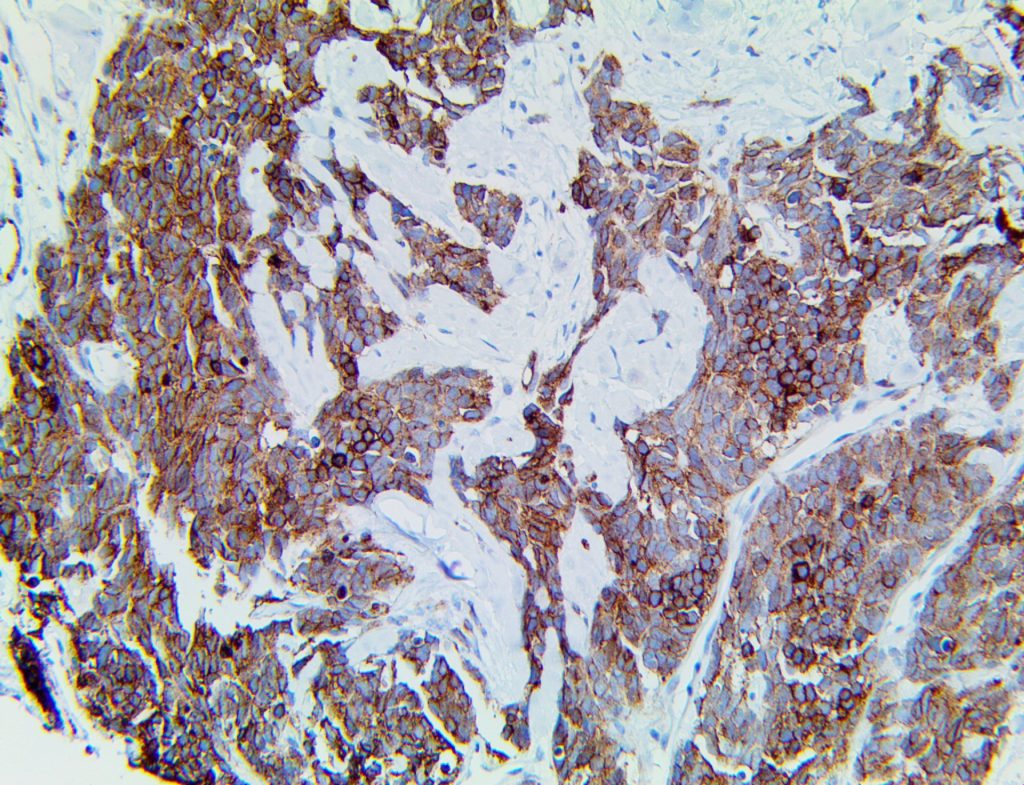

The first cytokines released are interleukin 1β (IL-1β) and tumor necrosis factor-α (TNF-α), which attract a variety of circulating white blood cells (WBCs) to the infection site, including neutrophils, monocytes, macrophages, and natural killer (NK) cells. This response, along with the antipathogenic chemicals released by these cells (i.e., complement), comprise the innate immune response. These cells directly attack the invading pathogen and also release additional cytokines, chief among them interleukin-1 and 6 (IL-6). IL-6 is essential for invoking the adaptive immune response, which calls T-cells, B-cells, and T helper (Th) cells to the infection site. IL-6 also stimulates further recruitment, proliferation and activation of macrophages.

This activation induces inflammatory monocytes to highly express IL-6, starting a localized and then systemic cascade effect that results in hyperproduction of IL-6, which accelerates the inflammatory process. Because IL-6 also increases vascular permeability, excessive levels cause blood vessels to become very leaky. This, along with clotting factors released from vascular endothelial cells, stimulates the coagulation cascade, resulting in microthrombosis (tiny clots), which leads to ischemia and tissue death of the kidney, intestines, heart, liver, brain and extremities.